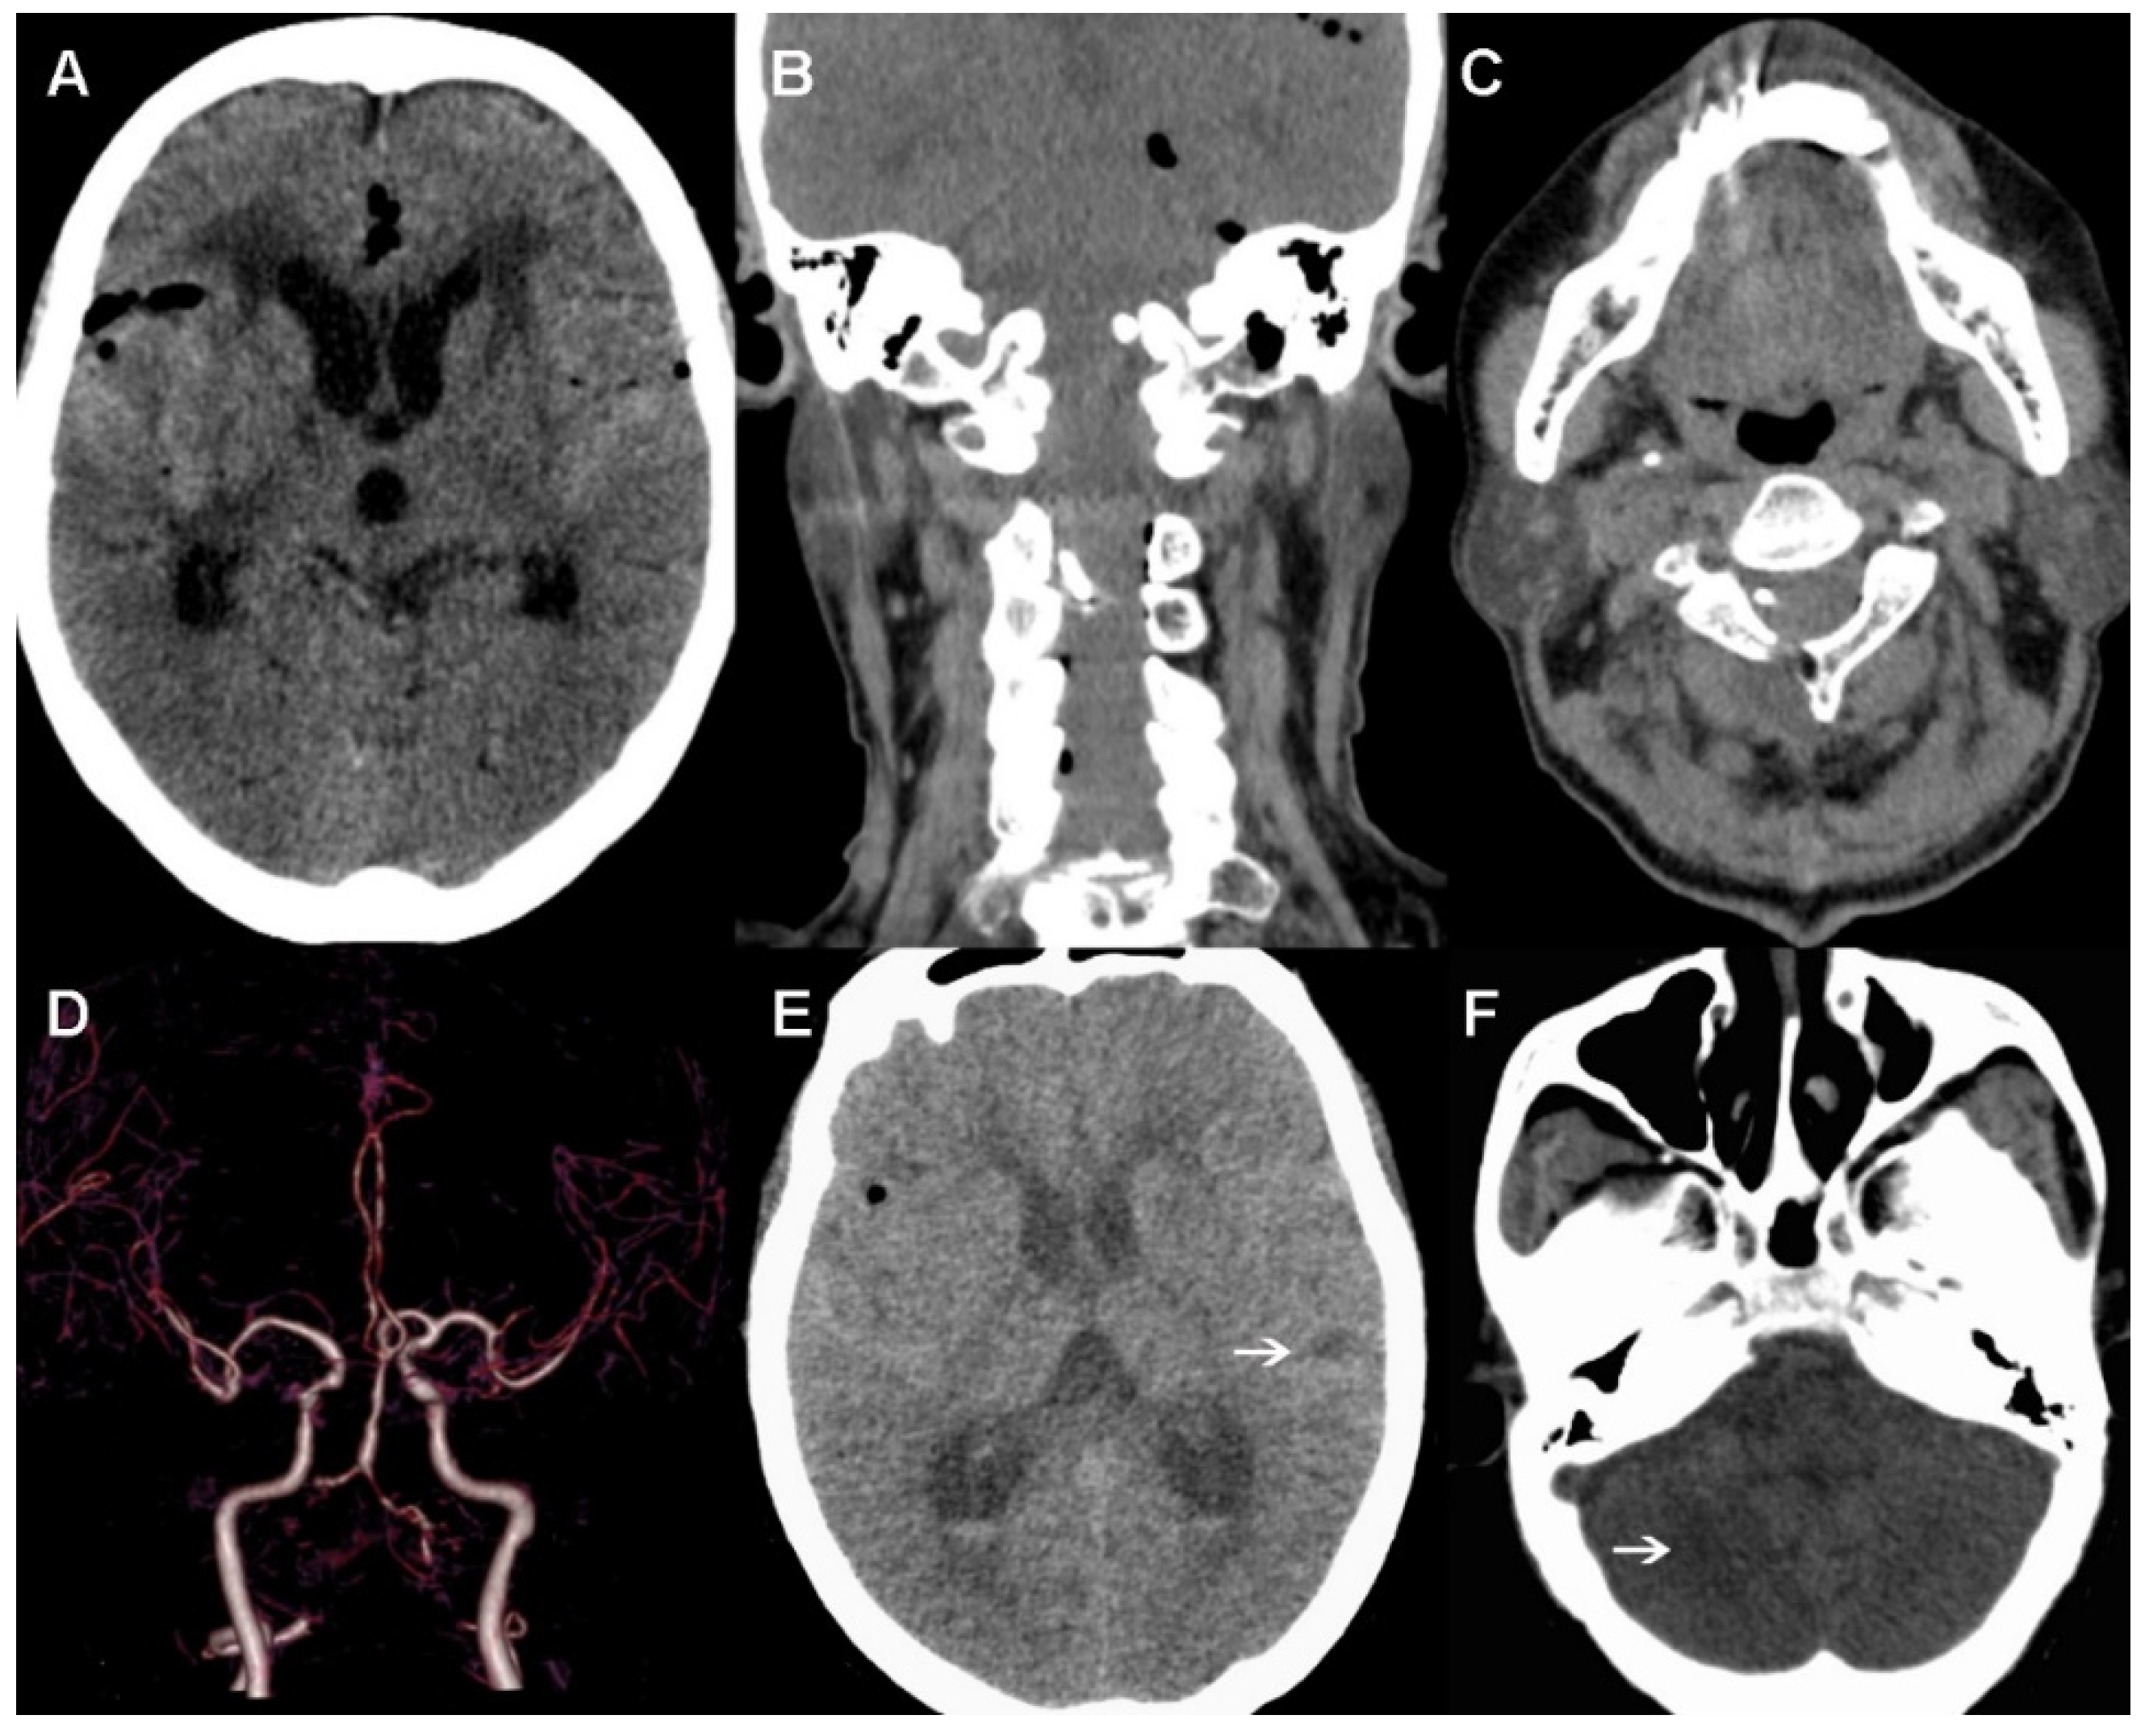

A scheduled CT was performed on the first postoperative day. As shown in Figure 4A–C, there was only a slight pneumocephalus, but no cerebral hemorrhage or infarction was observed, and the clip was well positioned. Furthermore, the neurological status of the patient remained basically unchanged for the first two days after the operation. However, the patient experienced a decline in consciousness at 3 days postoperatively. A head CTA confirmed aggravating cerebral vasospasm, especially bilateral VA and middle cerebral artery, and cortical hypodense changes were observed in the right cerebellum and left temporal cortex (Figure 4D–F). Therefore, we increased the strength of the anti-vasospasm treatment and performed a lumbar puncture to facilitate the drainage of bloody cerebrospinal fluid. In addition, anticoagulant therapy was also used to prevent venous thrombosis. Unexpectedly, the patient suddenly developed dyspnea, with severe oxygen desaturation and low blood pressure 7 days later. After emergency tracheal intubation and ventilator support, the patient’s vital signs gradually stabilized. However, over several hours, a sudden cardiac arrest occurred. Finally, her family refused further treatment and she died less than 1 day after leaving hospital.

Figure 4.

Postoperative images. (A–C) No cerebral hemorrhage or infarction is observed in the first day after surgery, and the clip is well positioned. (D–F) Cerebral vasospasm and cortical hypodense changes (indicated with arrows) found 3 days postoperative.